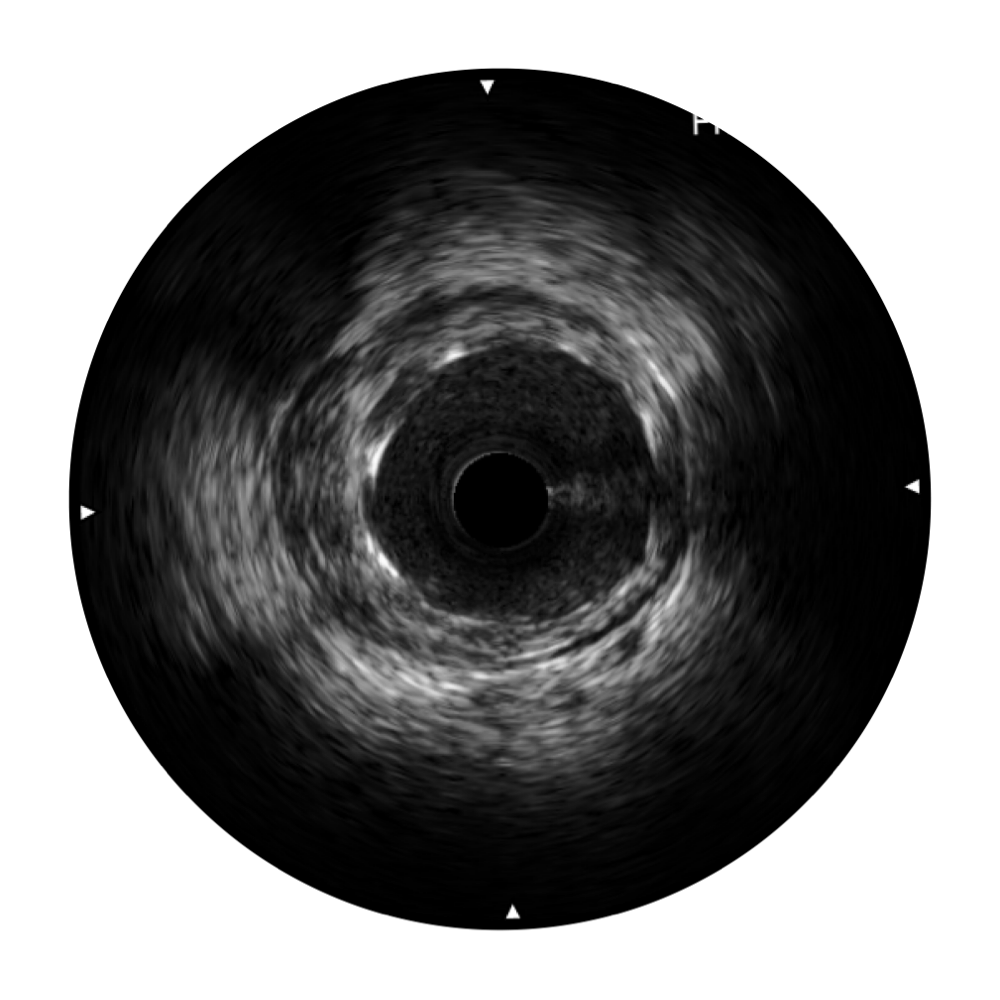

• 传统IVUS图像

对比传统IVUS导管成像,玖鼎集团宽频IVUS图像的近场支架梁显影更细腻,远场中膜外血管仍清晰可辨,兼顾远中近,兼顾分辨力与穿透深度